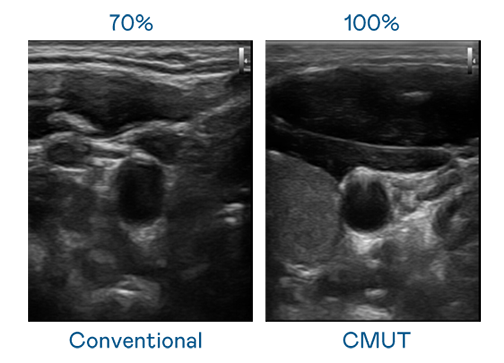

CMUT 技术是一种用电容式微机电元件来产生超音波讯号的技术。与传统 PZT 压电式技术相比,CMUT 频宽增加 30%,更宽频的超音波讯号让影像解析度大幅提升,是实现高影像品质医疗超音波扫描、促进精准医疗发展的关键技术。

大频宽带来超清晰影像

超音波影像的解析度高低,首先取决于探头能发出的讯号频宽。熊猫体育 CMUT 可提供高清晰的超音波讯号,提供高频宽、高灵敏度、影像纹理细节更高的超音波影像,协助医护人员缩短影像判读时间及利用精准的医疗影像进行诊断。